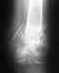

Приложил холод и поехал в районный травмпункт. Сделал рентген.

Врач поставил диагноз: "З/перелом 5 плюсневой кости б/с". Снимок мне, увы, не показал. Наложил лангету.Лечение - иммобилизация, без нагрузки, кальций+д3.

Сегодня 40 день (почти 6 недель) с момента перелома, сделали повторный снимок. И неожиданно врач говорит что "смещение стало меньше" и "сращение недостаточно". И прописал еще две недели в лангете. Однако при этом советует отказаться от костылей и ходить опираясь ПОЛНЫМ весом на всю ступню (а не только пятку, например). При этом у меня до сих пор сильные боли в районе мизинца (сбоку и снизу стопы) и гематома в половину ступни в районе трех центральных пальцев.

Прикладываю снимки рентгена на 40 день перелома.

Перелом срастается в приемлемом положении.

Можно увеличивать нагрузку на ногу в пределах переносимого. Смысла в гипсовой шине при полной нагрузке не видно - гипс немедленно сломается.

По мере того, как уйдут болезненные проявления, можно будет возвращаться к спортивным нагрузкам.